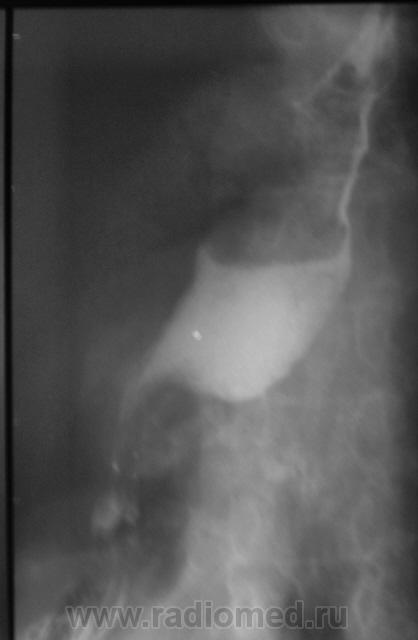

Пациентка, весьма преклонного возраста направлена на исследование желудка. Диагноз - язвенная болезнь желудка. Ну с желудком вроде-бы нормально, но вот с пищеводом возникли заморочки. Все осложнилось еще и тем, что пациентка в вертикальном положении смогла побыть секунд 40.

Ниже снимки, которые смогли провести в положении стоя.

ахалазия пищевода...

Похоже что в нижней трети пишевода чтото "живёт"

Озлокачествленная лейомиома пищевода.

Ну, лейомиому, мы написали в протоколе.